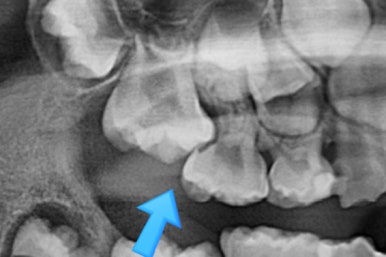

부산어린이치아교정 키다리아저씨치과에 처음 내원하셨을 당시의 X-ray 사진입니다.

이 때는 7세 3개월 때였습니다.

보통 만 6세 부터 아래 앞니 부터 영구치가 나기 시작하며, 비슷한 시기에 유치보다 더 뒤에 영구치 어금니가 나오게 됩니다.

이번 환자분은 제 나이보다는 치아나이가 어린편이어서 다른 부위의 어금니도 나오지 않았긴 하지만 치과 검진에서 우연히 해당부위(화살표)의 치아가 문제가 있음을 발견하셨던 경우입니다.

만 6세 이후 반드시 X-ray 찍어보시기를 추천드립니다.